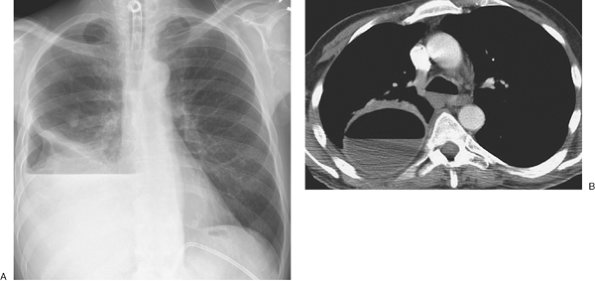

FIGURE 9-5. Cerebrospinal fluid leak into pleural space. A: PA chest radiograph of a 42-year-old man who recently underwent partial corpectomy of the thoracic spine at several levels shows complete opacification of the right hemithorax and shift of the mediastinum to the left. B: Non–contrast-enhanced CT shows a large right pleural effusion, collapse of the right lung, mediastinal shift to the left, findings of corpectomy, and continuity of fluid from the spine into the pleural space (arrow).